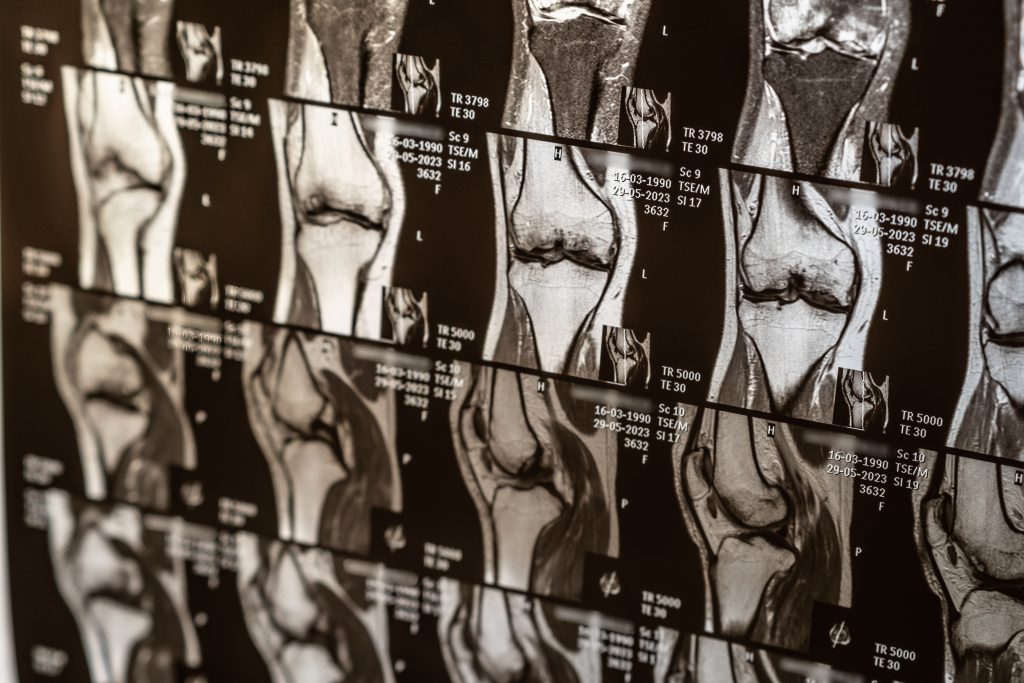

A ressonância magnética é considerada o padrão ouro no diagnóstico da lesão no menisco. Isso porque ela permite a visualização detalhada das estruturas internas do joelho — incluindo cartilagens, tendões, ligamentos e músculos — sem o uso de radiação ionizante.

Diferentemente de outros exames, como o raio-X, que só mostra ossos, a ressonância magnética fornece imagens em alta definição das partes moles. Isso torna possível identificar até mesmo pequenas rupturas no menisco que poderiam passar despercebidas em outros métodos.

As imagens obtidas permitem identificar lesões no menisco, como rupturas, além de avaliar ligamentos, cartilagens e outras estruturas articulares do joelho. É importante que o paciente permaneça imóvel durante toda a realização do exame, que costuma durar entre 20 e 40 minutos.